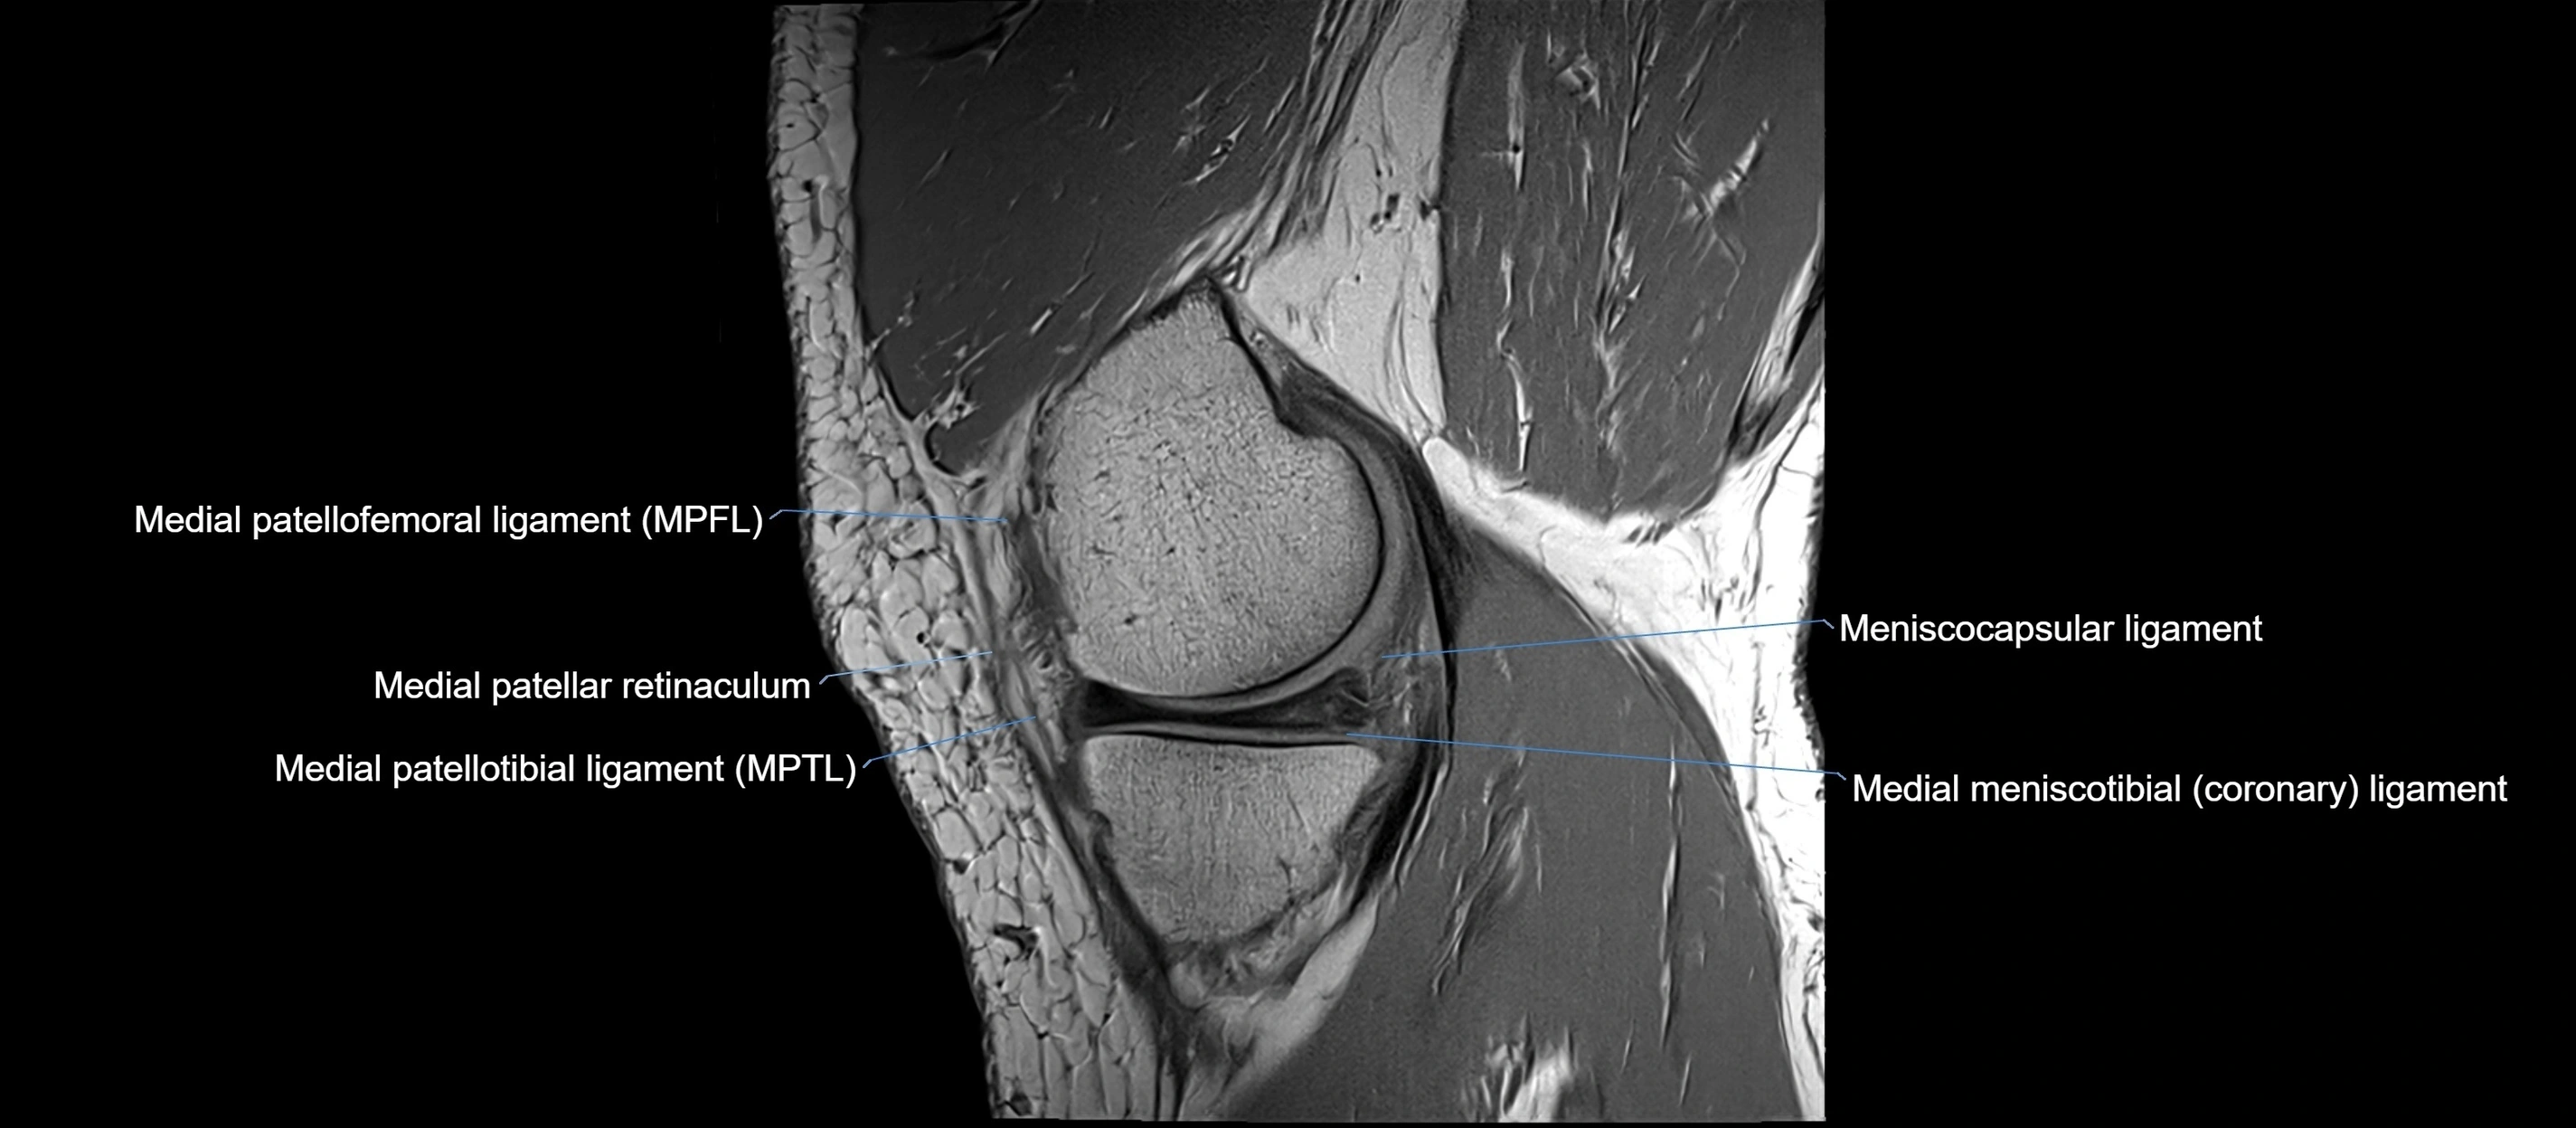

MRI images

image